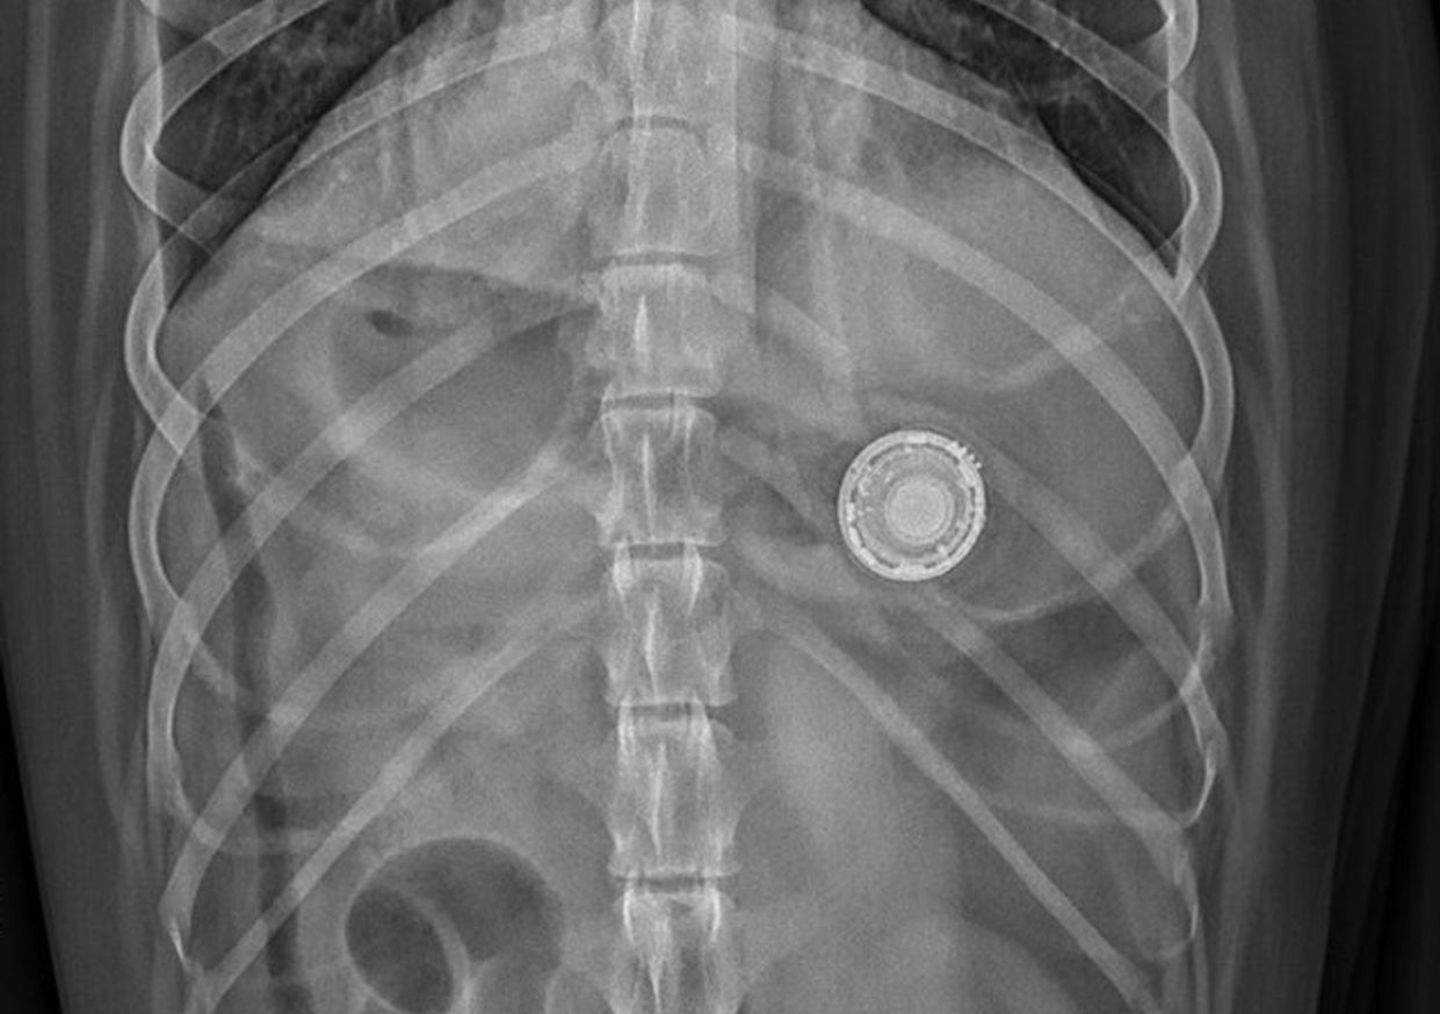

Gràcies a The Wall Street Journal que ens explica moltes històries sobre gossos i AirTag, es demostra que el rastrejador d'Apple pot ser ingerit per error. Per exemple, una propietària va haver de rastrejar el seu AirTag fins que va sentir el xiulet a l'estómac de la seva gossa Sassy. Una altra història indica que una gossa anomenada Rose va mastegar el dispositiu i lamentablement va menjar trossos de metall i plàstic de l'interior. La història més tràgica en el moment d'ingerir-lo va ser la de la Luna. Per més que va intentar vomitar-lo es va intentar una cirurgia que no va ser exitosa. A les setmanes del succés, la Luna va vomitar el dispositiu.